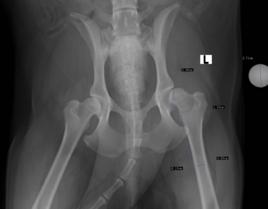

診斷方式主要是通過x光拍攝進行診斷,又分為早期診斷與後期診斷。早期診斷的拍攝x光方式有很多種,普遍被人認可的是美國賓西法利亞大學推廣的pennyhip方法。另外有背側髖臼緣角度(dorsal acetabulum rim angle,DARA) 。國際上有ofa標準的評分方法是在犬24月齡的時候拍攝2張標準的x光片(腹背位和腹背位蛙式),通過髖關節與股骨頭的位置關係和關節的炎症程度對犬進行評分。但是在臨床上,對2歲的成年犬進行診斷已經很晚,髖關節形態結構已經形成。